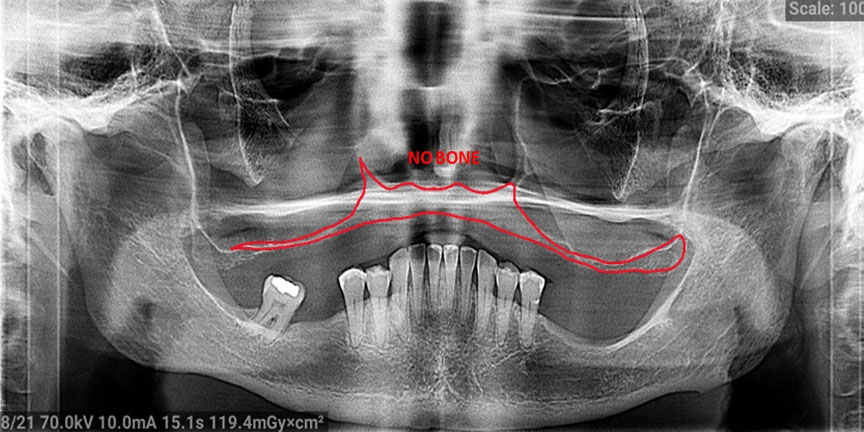

Expertise with Complex Cases: We handle challenging cases that other providers may struggle with, offering solutions where others cannot.